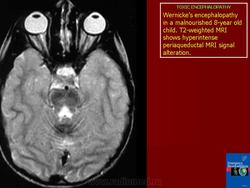

Энцефалопатии токсикогенные

Спасибо, Валентин Львович! Алькогольную встречал несколько раз, у относительно молодых пациентов. Без анамнеза и клинической картины, энцефалопатии очень сложно дифференцировать, если не попадется патогманичного признака.